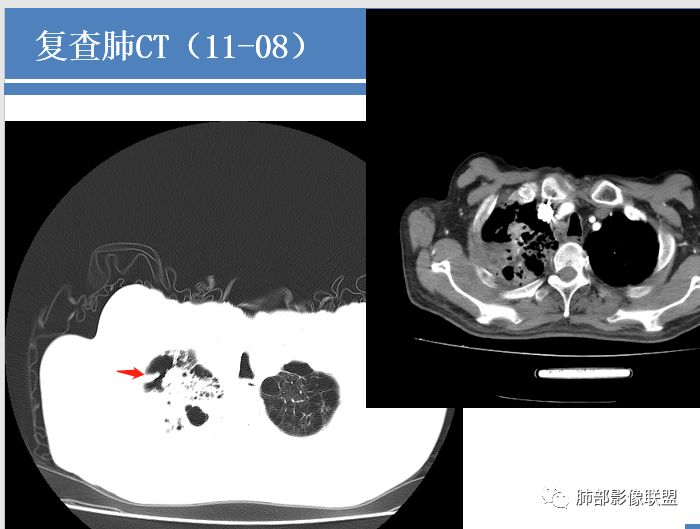

病例分析:双肺肺气肿,肺大泡,右肺上叶大片实变及空洞影,空洞壁光滑,部分有液平,病变自胸膜下向内,胸膜增厚,右肺下叶实变伴有空洞,右侧胸水,右肺门淋巴结肿大 ,抗炎治疗后变化不大,临床起病一周,有发热,血沉及降钙素高,肿瘤标志物稍高,结核干扰素阳性,首先考虑结核,鉴别细菌(空洞有液平)。

肺气肿,肺大泡背景,一周前出现症状,右肺上叶网格状及条片状病变,渗出为主。抗炎一周复查,范围加大,右侧胸水增多。再次复查,左肺上叶尖后段亦出现高密度影。增强扫描右上肺病变实性部分似乎没有强化。结合临床实验室检查,考虑结核可能性大。

老年男性,起病急,感染指标高,肺部CT示肺气肿征象,双肺见肺大疱,感染病灶。予以碳青霉烯抗感染病灶出现明显进展,出现虫蚀样空洞、气液平。考虑患者细菌感染合并结核可能性大。但是结核进展可能太快了,需要排除真菌。

如果没有结果,分析是这样:这个人肺气肿基础,出现大片实变,那符合气肿性肺炎,头两次影像上还看不出结核来,但是白细胞不高,中性粒仅仅高一点的,然后血沉高,R干扰素高,抗感染不好。然后这个人有老年痴呆,初期可能会考虑这个人会不会只是一个细菌性肺炎呢,进展快。入院常规给与抗细菌没有问题。但是到11.08号影像出现一些端倪。一般气肿性肺炎虽然说可能好的不那么快,但是给与了亚胺培南这么高级的药反而进展,再加上血常规和一些实验室检查,好像普通细菌感染就有一点说不过去了。到第三次,出现空洞了,和肺气肿肺炎的气肿已经不一样了,气肿随着实变增加,里面应该会填实才对,但是出现空洞,这个说明不再是气肿里面的,而是真的空洞,而且还是那种肺尖的、光滑、有壁结节的空洞。

增强后里面密度整体低,比较支持坏死,一般炎症强化比较高,会有毛细血管新生,这个强化太低,提示坏死性炎症。这个还蛮符合干酪样坏死,实验室也支持。结核我感觉肯定有。